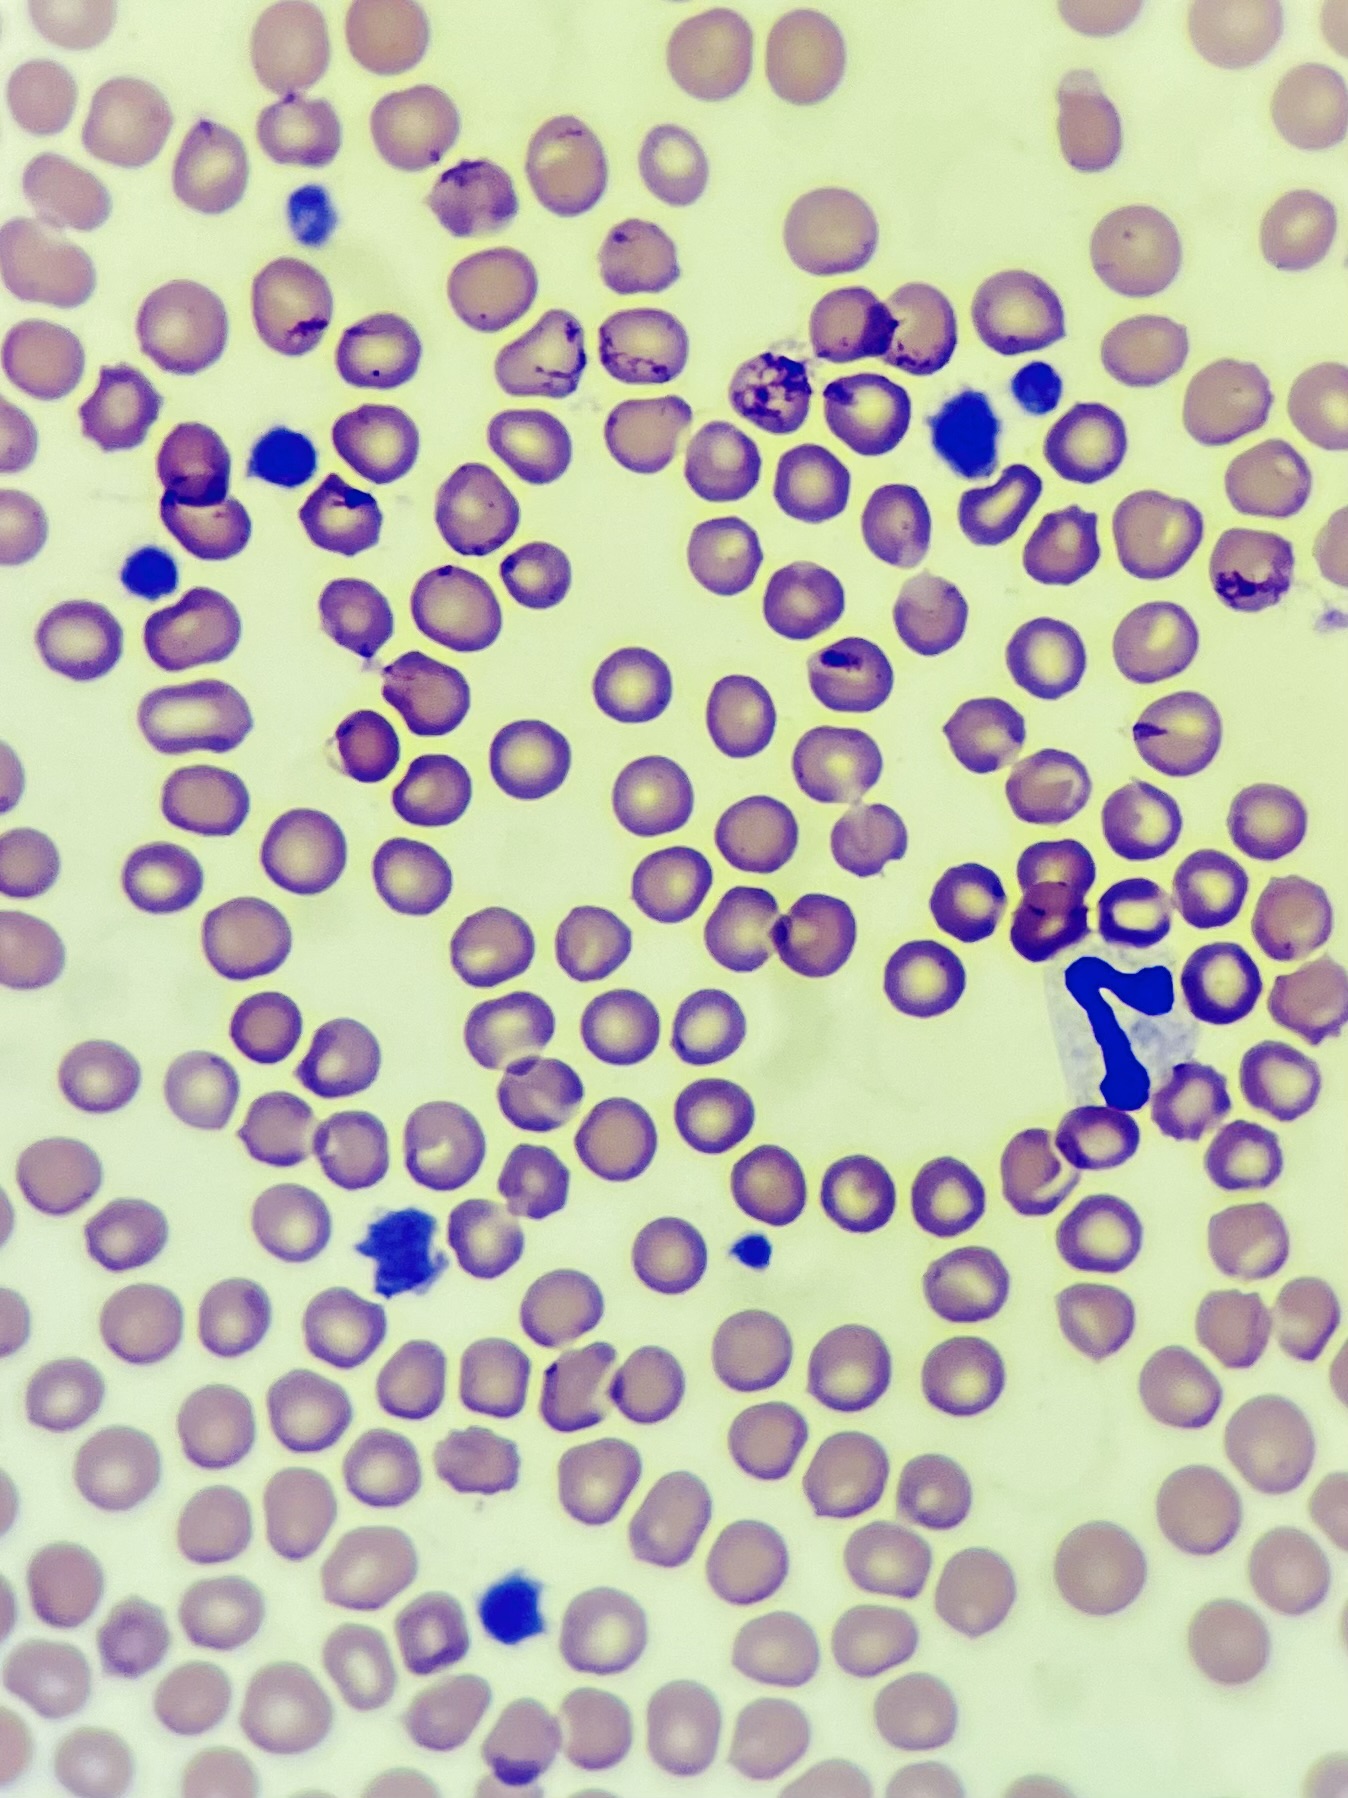

Parasite control

Parasites, both internal and external, pose a threat to our pet’s health. Here at Whisker & Woof, we take parasite control seriously, and always make a recommendation to protect your pet. Fleas, a relatively minor affliction in healthy adult pets, can cause life threatening anaemia in the very young. Ticks, more prevalent in particular wooded areas, can transmit Lyme’s Disease. Of most concern is lungworm, the most common of species of which is Angiostrongylus vasorum, which can cause bleeding and respiratory distress, and can be fatal. We can offer tailored advice as to which products would suit your particular pet and his or her lifestyle.